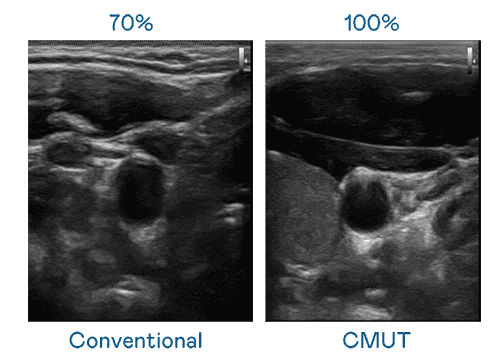

CMUT 技术是一种用电容式微机电元件来产生超音波讯号的技术。。。。与传统 PZT 压电式技术相比,,,,CMUT 频宽增加 30%,,,,更宽频的超音波讯号让影像解析度大幅提升,,,,是实现高影像品质医疗超音波扫描、、、、促进精准医疗发展的关键技术。。

超音波影像的解析度高低,,,首先取决于探头能发出的讯号频宽。。Wepay CMUT 可提供高清晰的超音波讯号,,,,提供高频宽、、、、高灵敏度、、、、影像纹理细节更高的超音波影像,,,,协助医护人员缩短影像判读时间及利用精准的医疗影像进行诊断。。